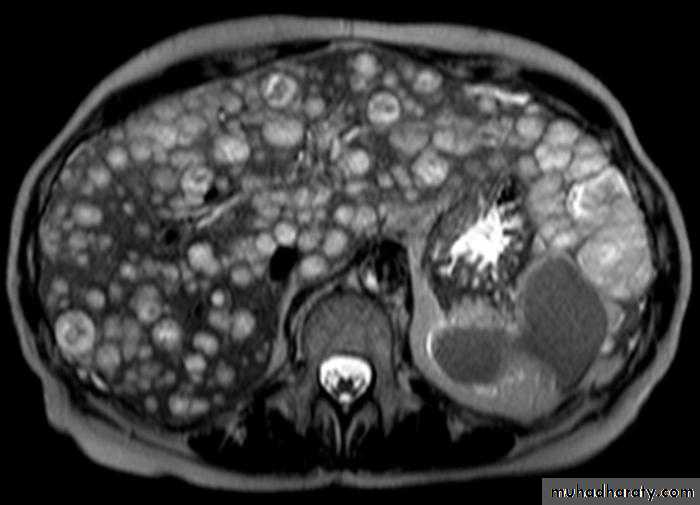

Multiple masses

MRI